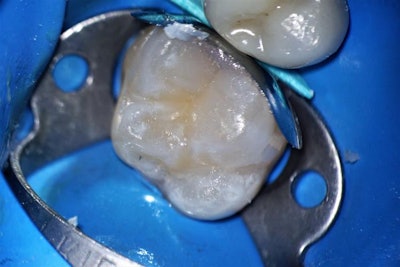

A sectional matrix band was placed and the preparation was selectively etched with primer and blue etch for 10 seconds only on the uncut enamel. An immediate dentin sealing technique was performed using Clearfil SE Protect (Kuraray Noritake Dental) according to the manufacturer's instructions for use.

This was followed by a resin coating using Clearfil Majesty ES Flow, then placement of a layer of Clearfil Majesty ES-2 Premium Dentin A2 to cover the dark stain in the dentin. In this type of case, using a darker shade of flowable resin in a dentin shade will easily mask the color and recreate the natural tooth appearance.

A stratification technique was used to restore the tooth by layering the universal composite in approximately 0.5-mm increments, polymerizing each layer with a curing light before applying subsequent layers. The composite used eliminated the need for a blocker shade, streamlining the procedure.

After completing the composite buildup and shaping the occlusal surface, the matrix band was removed for the final cure of the buccal, lingual, and occlusal surfaces. Polishing and finishing was accomplished with a pop-on disc used with a polishing cup and brush.